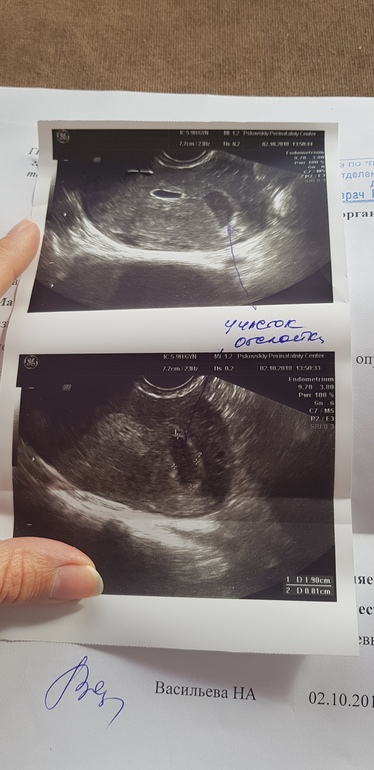

Результаты: УЗИ, КТГ, доплера, скринингаНу вот не зря поползла на УЗИ. ( ПЯ. нашли) туточки оно. Эмбрион не увидели ещё ((,но врач сказала, что -то проклёвывается,🐣но пока она не будет отмечать. Зато нашли отслойка!.🤨..мать её, собираю пожитки и в больницу. Симптомов никаких не мажет,не болит...теперь уж в больничке наковыряют(((( Год назад не спасли мне там мою Б. Но в этот раз я верю в лучшее)👶Фото УЗИ ПРИЛАГАЮ,жду поддержки...и рассказов у кого было также??